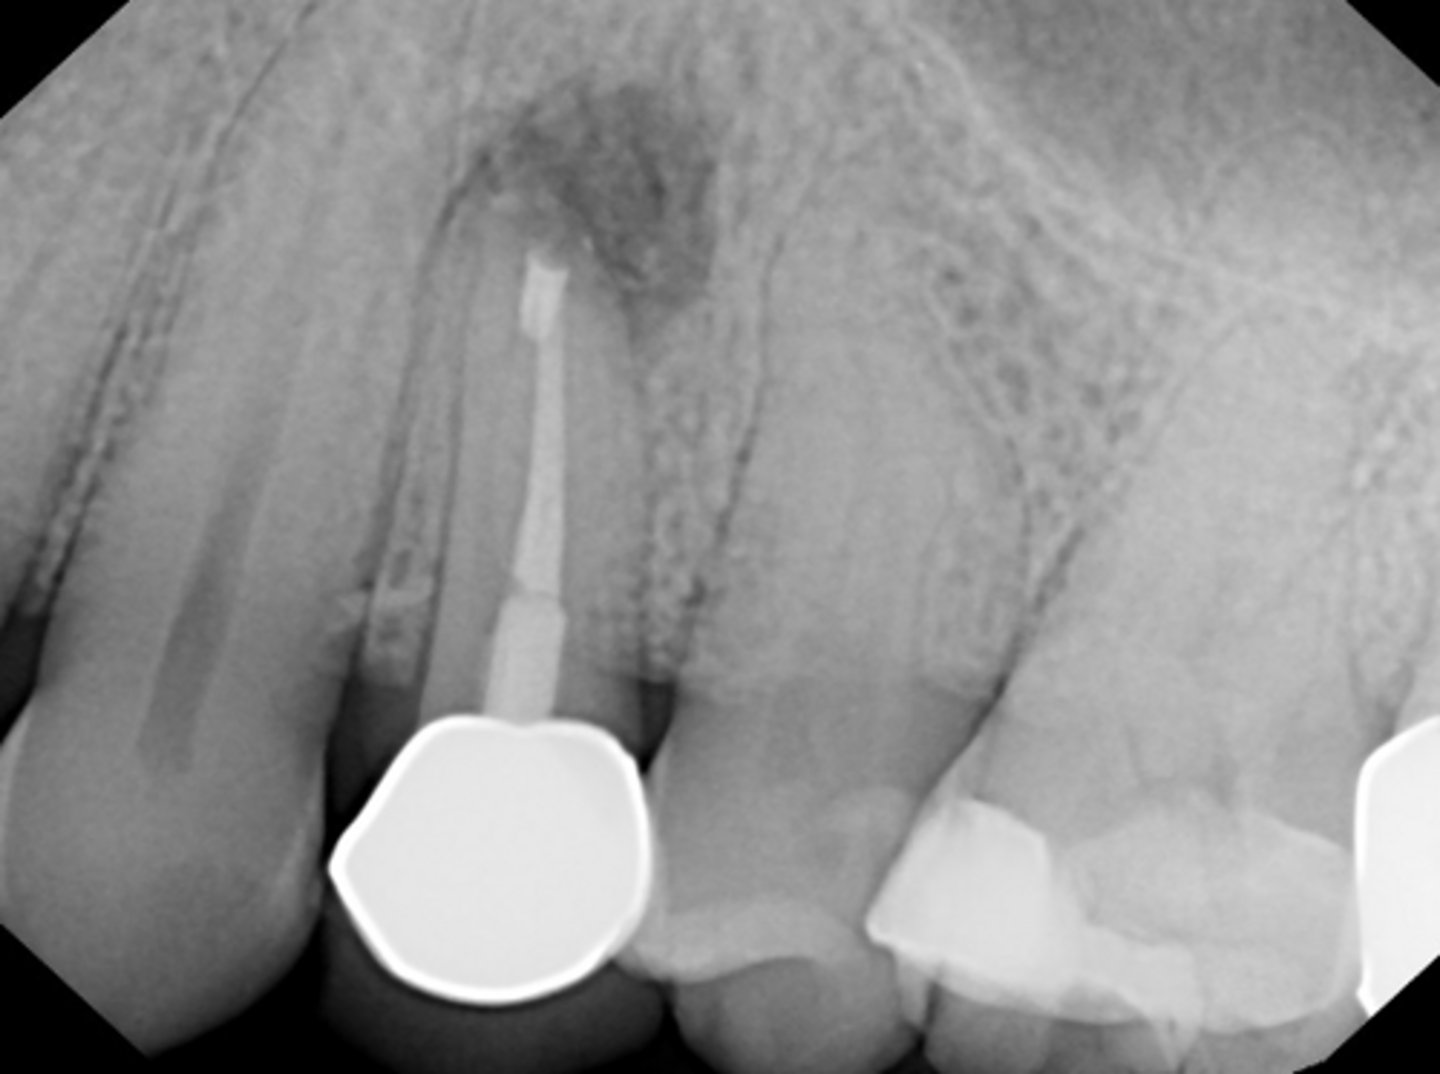

separated instrument

ID the procedural error: